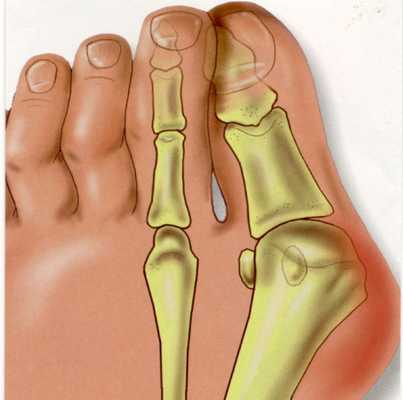

Вальгусная деформация стопы — комплексное заболевание, которое проявляется поперечным и продольным плоскостопием, искривлением первого пальца, образованием костной «шишки» и нарушением собственного мышечно-связочного баланса. [2] [6] [13]

Заболевание сопровождается уплощением стоп и их «заваливанием» на внутреннюю часть.

В результате ослабления мышечно-связочного аппарата стопы и неправильной нагрузки происходит изменение точек опоры и уплощение поперечного и продольного сводов.

Нагрузка и опора переходит на все плюснефаланговые суставы, что приводит к веерообразному расхождению костей переднего отдела стопы. [4] [15] Происходит дисбаланс мышечной силы, которая держит первый палец ровно, в результате он отклоняется, и искривление прогрессирует.

Значимым смещением костей первого пальца кнаружи считается смещение более чем на 10 градусов. Параллельно изменения происходят в капсульно-связочном аппарате — растяжение наружных отделов, смещение сесамовидного гамака. [6] [13]

Еще поперечное распластывание способствует развитию метатарзалгии — болей в области II-IV плюсневых костей из-за избыточной нагрузки, так как в норме в переднем отделе основная опора приходится на головки I и V. [5] [8]